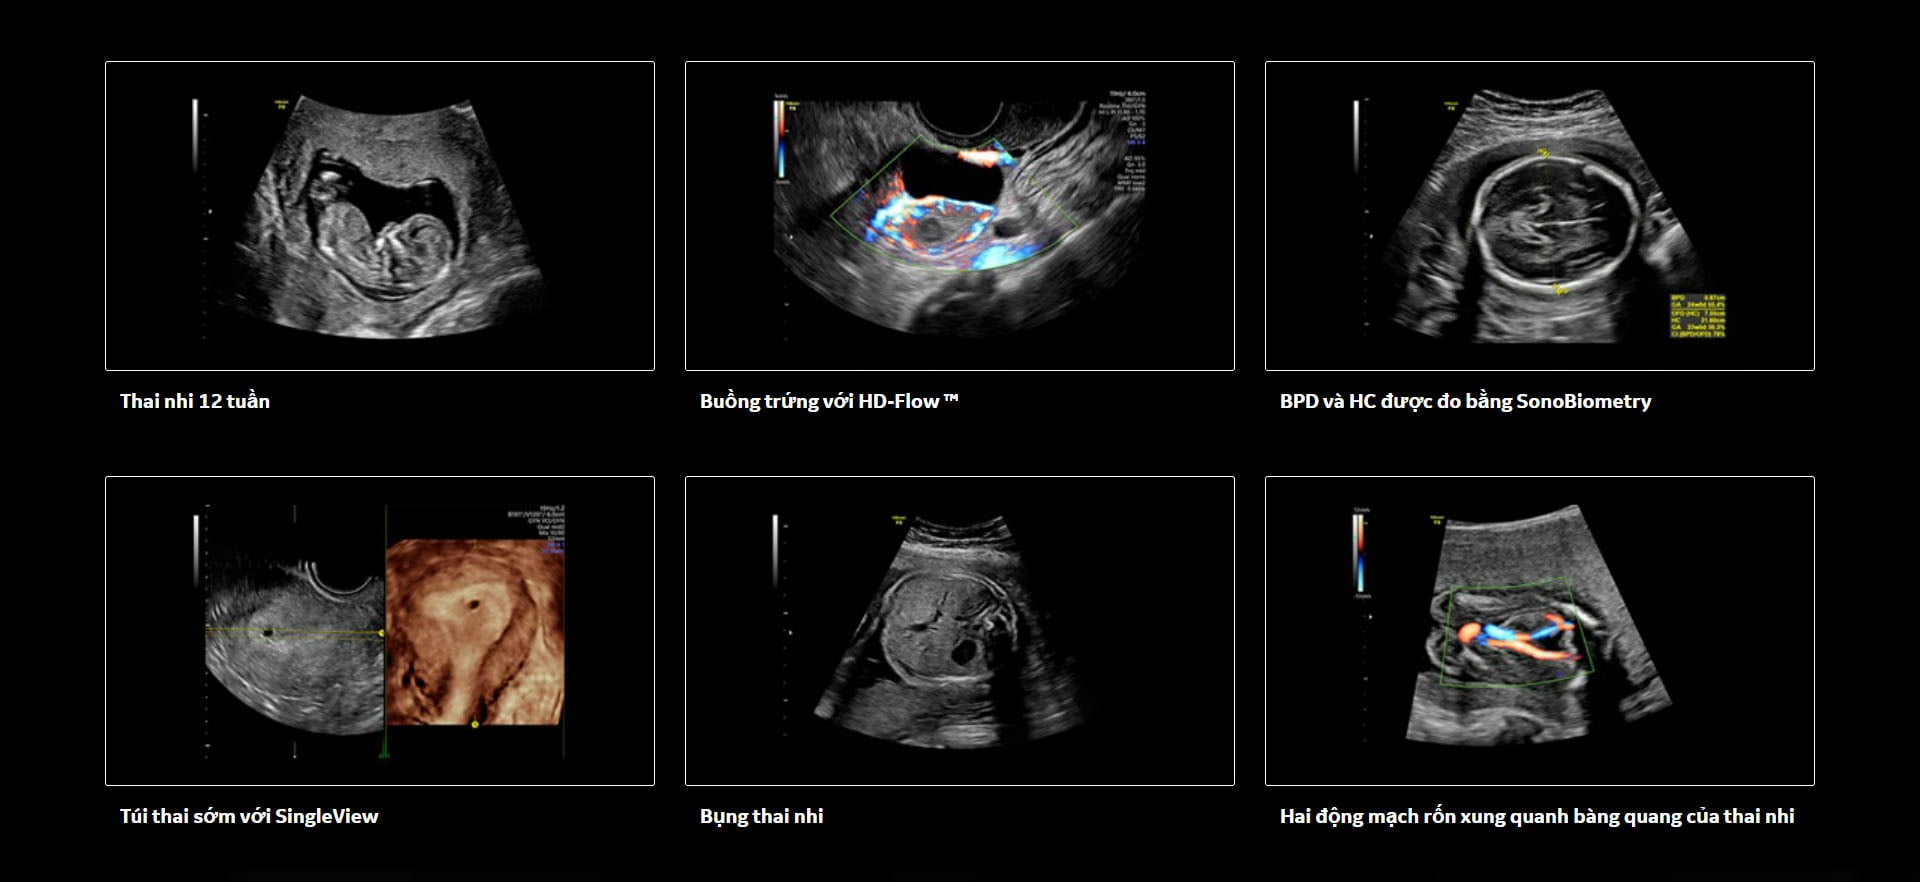

Hình Ảnh Lâm Sàng

Ứng dụng của Voluson P8 bao gồm sản khoa, phụ khoa, y học hỗ trợ sinh sản, chuyển dạ & sinh nở.